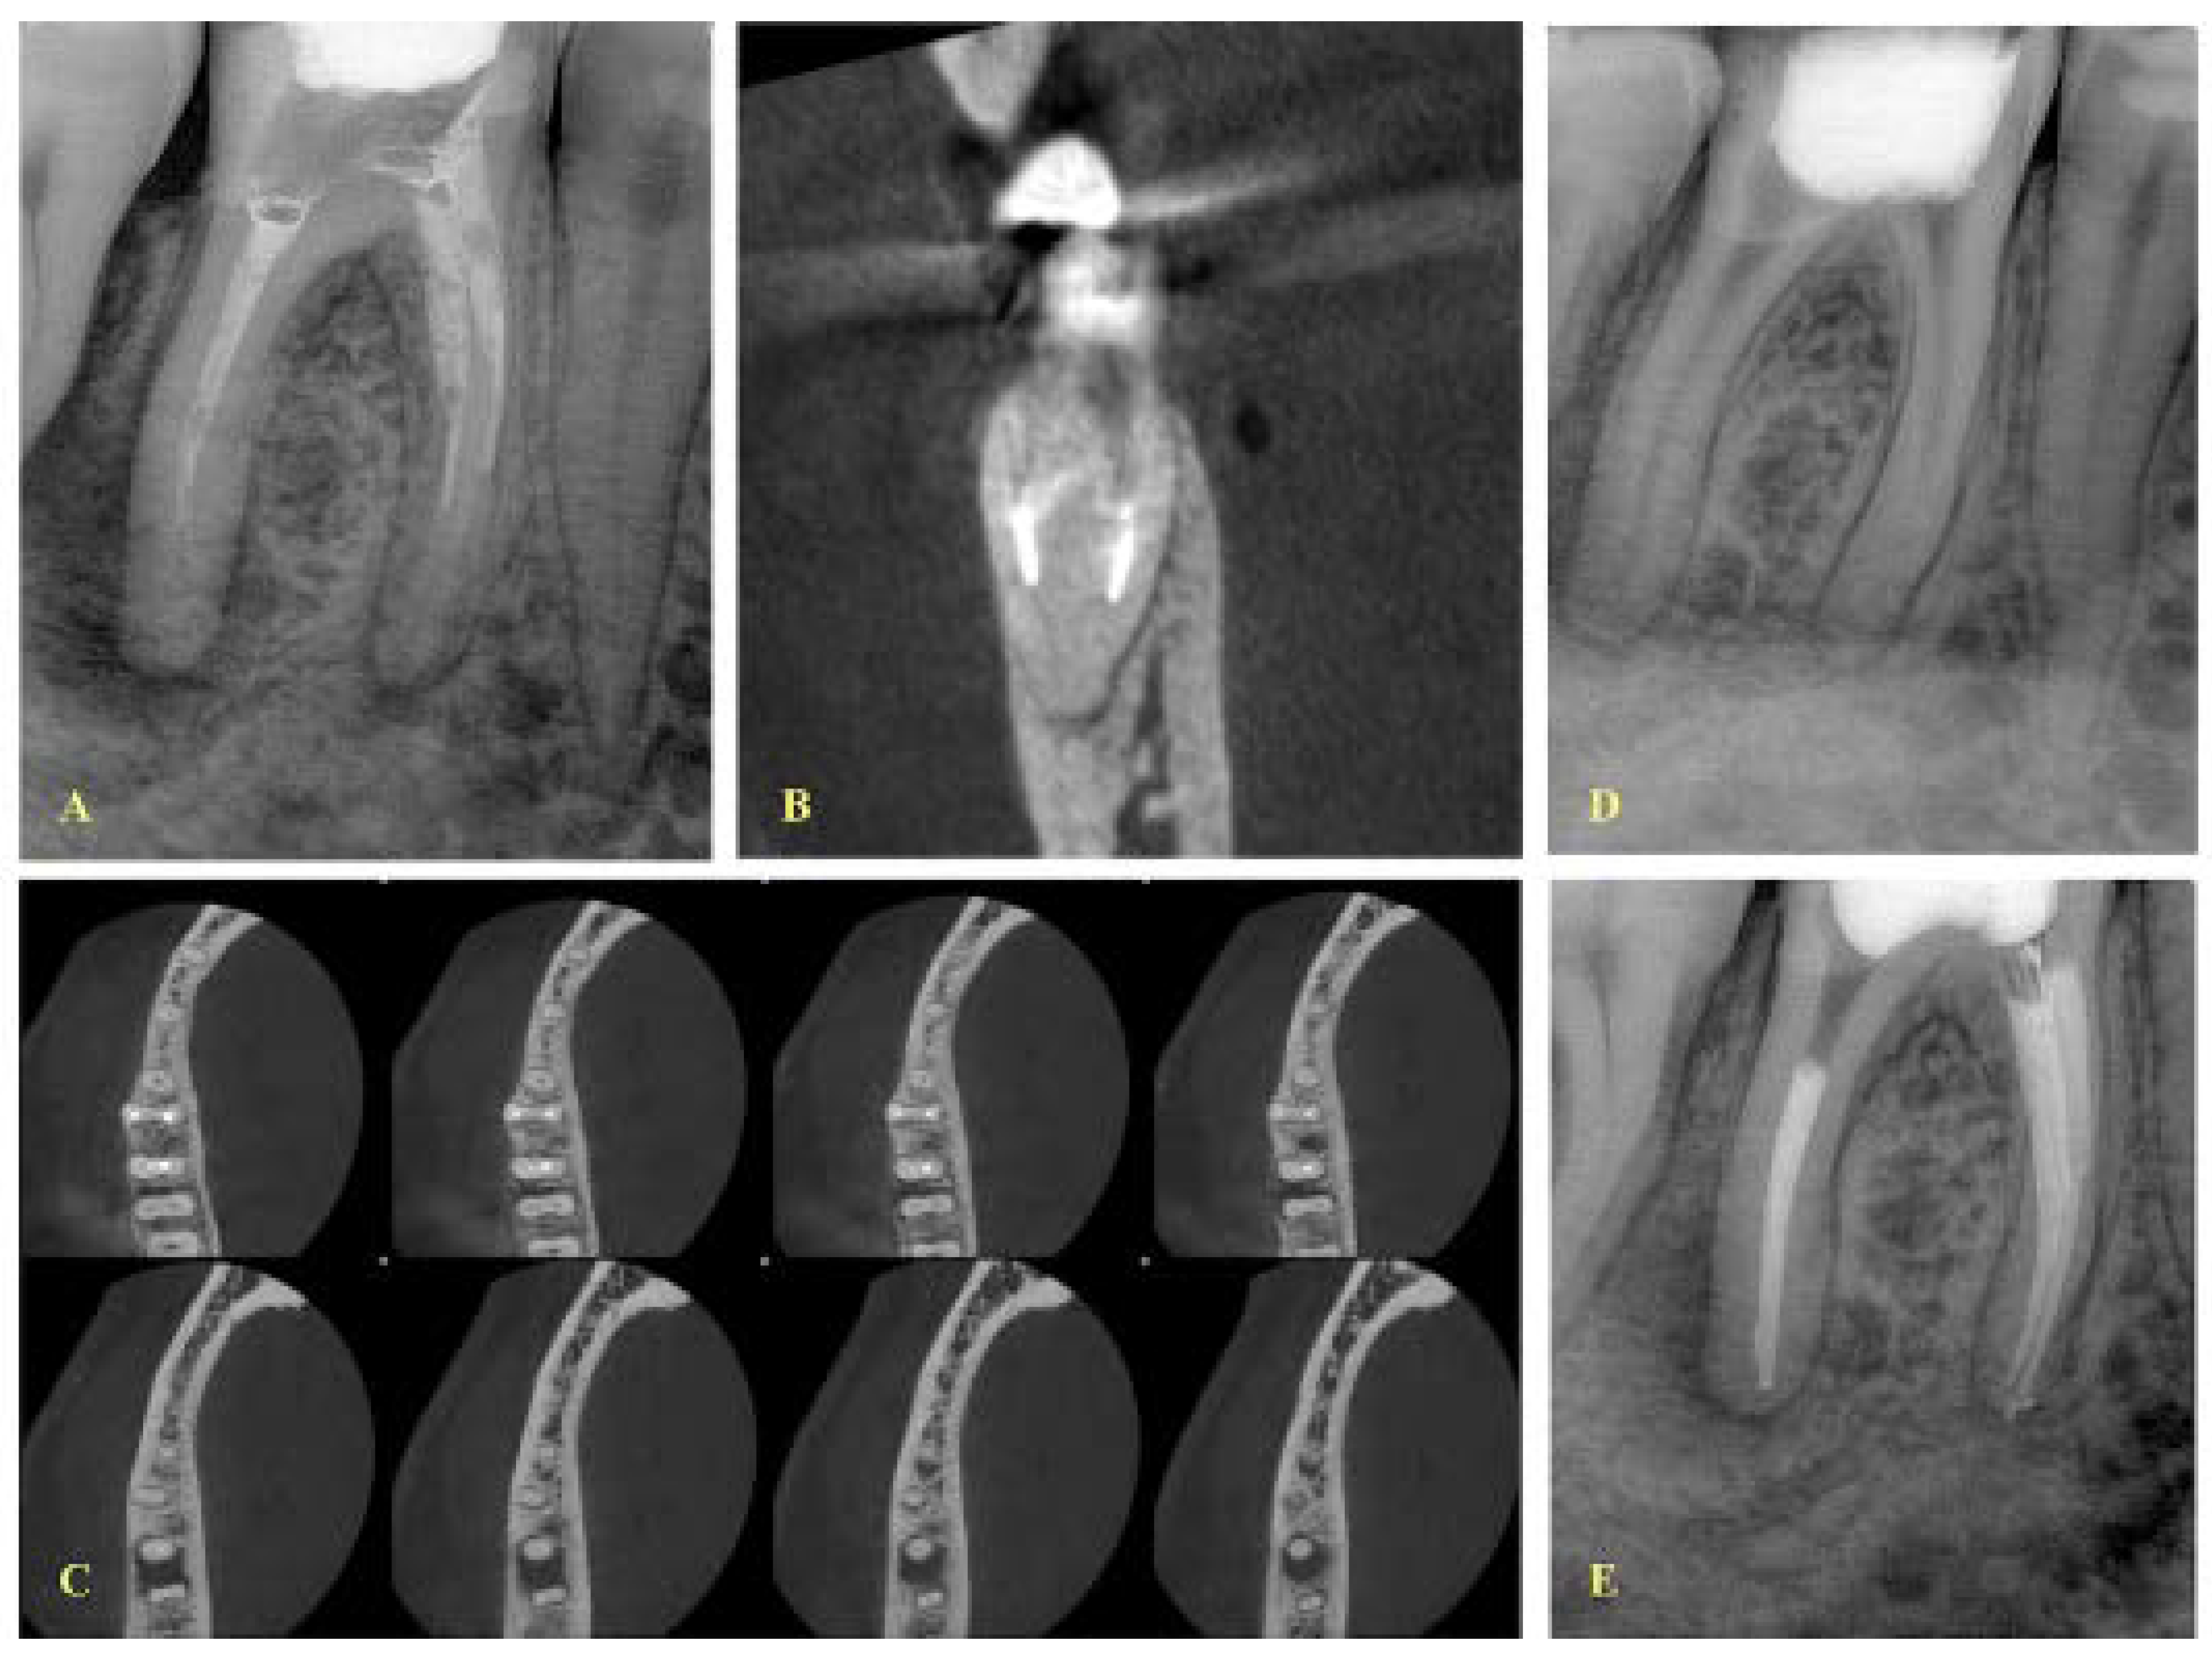

- If a lesion was present, the canals were separate and the fragment was located at the apical level, and a final treatment plan of bypassing the fragment was set (Figure 1).